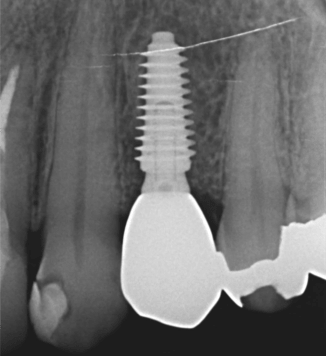

症例3【40代女性】右上74根尖病巣の治療 右上56 洞低膜を挙上しインプラント埋入

治療後(5年経過)

主訴 右上で物が噛めない。インプラントを希望され来院。

右上第二小臼歯はC₄にて抜歯。右上第一大臼歯は欠損の状態。

残存骨が5~6㎜程で、インプラント埋入には骨の高さが不足している為、ソケットリフト(骨造成)を行った。洞底膜を挙上することで、骨の高さの不足を解消。

採血のよるCGFメンブレンとAFGブロック(人工骨β‐TCPとAFGを混ぜたブロック)を填入しインプラント2本を埋入。約4ヶ月の免荷期間を経て、仮歯を装着、リハビリをし、約5ヶ月後にメタルボンド(金属焼付ポーセレン)を装着。

リスクとしては、ソケットリフト(骨造成)による一過性の副鼻腔炎が起きる可能性がある。まれに洞底膜が破れる可能性がある。ただし、膜は約3週で再生するので、膜の回復を待ち、再オペを行う。

費用 113万(オペ・ソケットリフト・人工骨・採血による濃縮血小板生成・仮歯・最終補綴物まで含む)